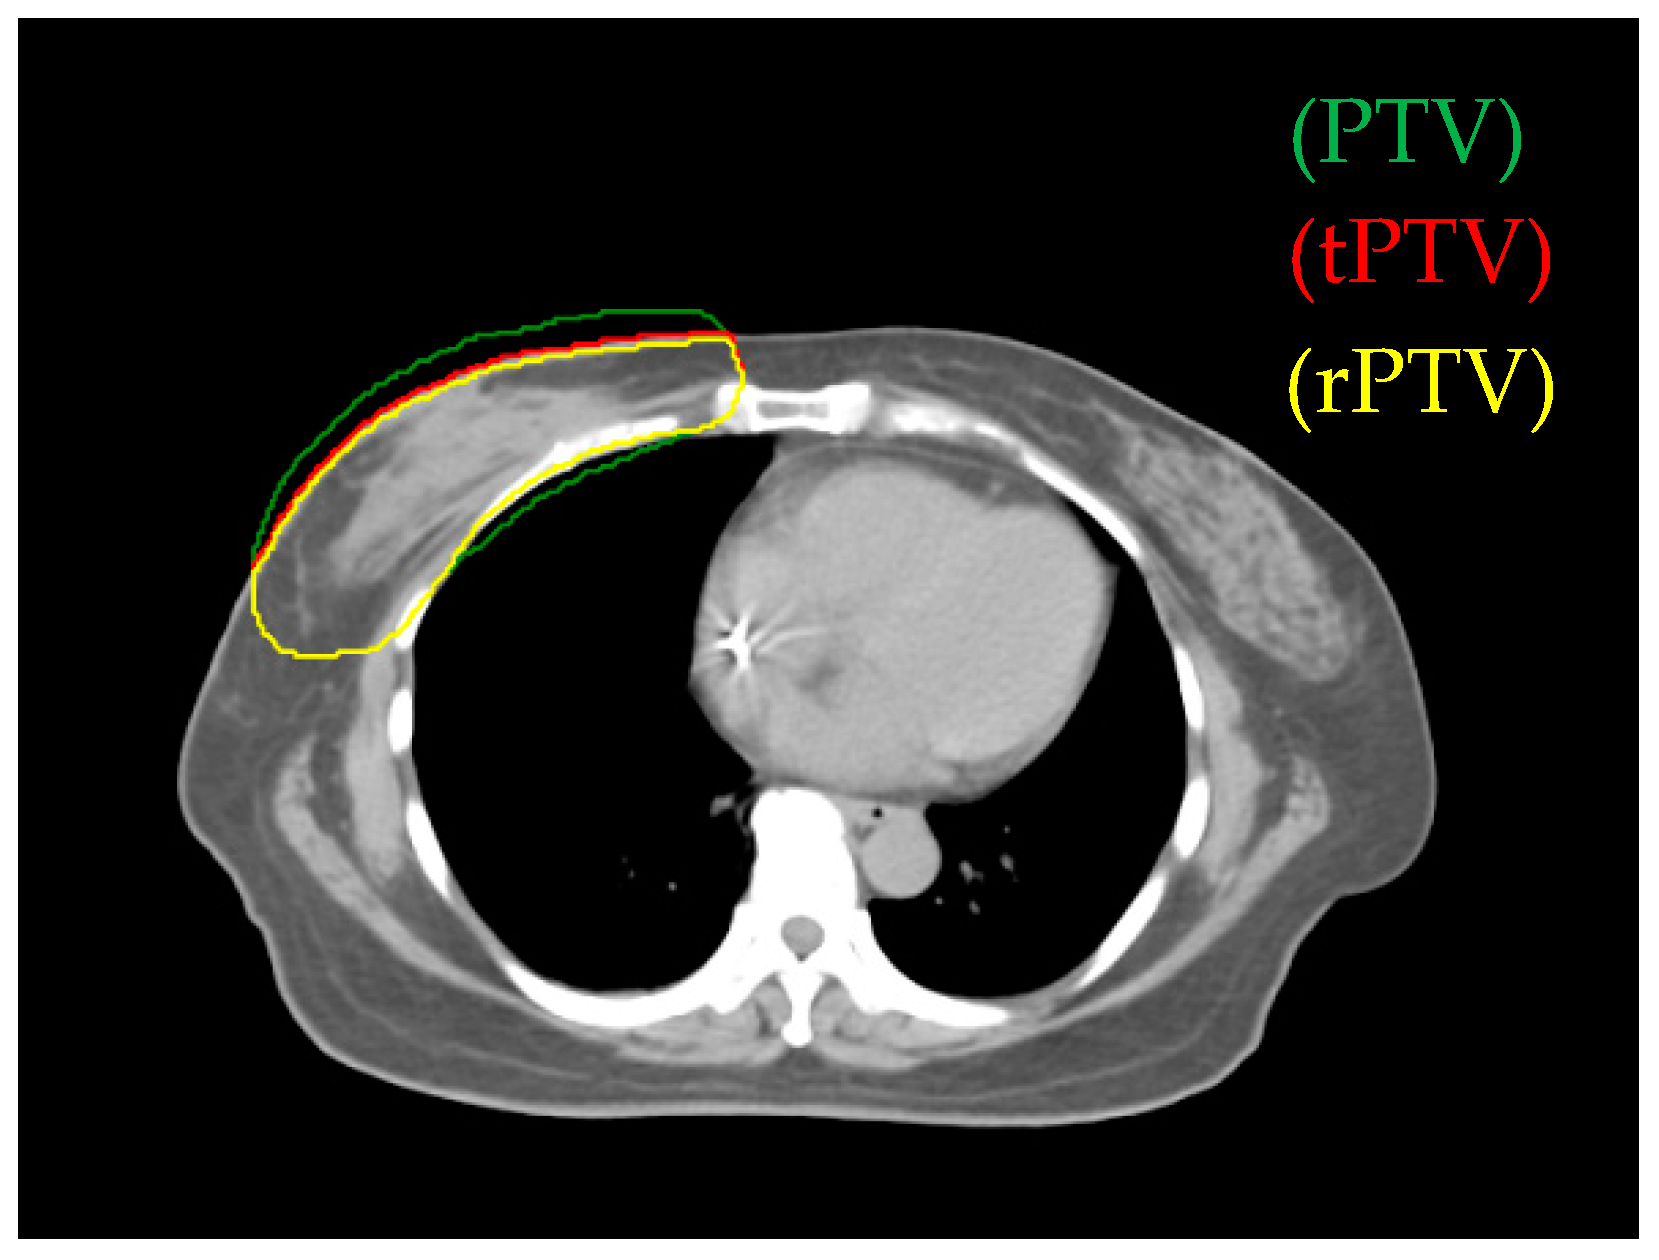

2.3. Target Volume and Planning Organs-at-Risk Definition

3.1. Comparison of Reduced PTV (rPTV) in Four Techniques on Dosimetry